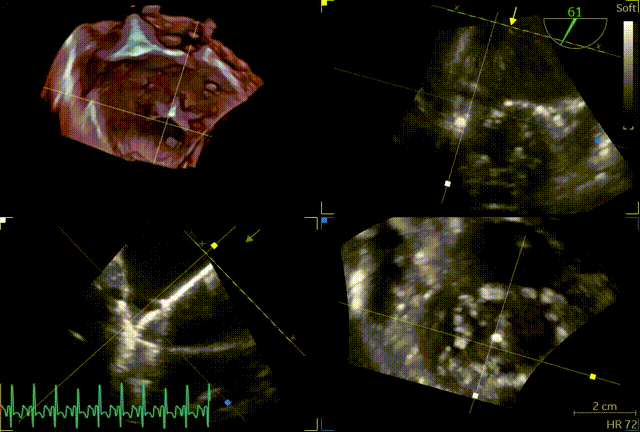

3D

3D带彩

3区gap

3D辅助辅助观察点位

穿刺高度

3D复测穿刺高度